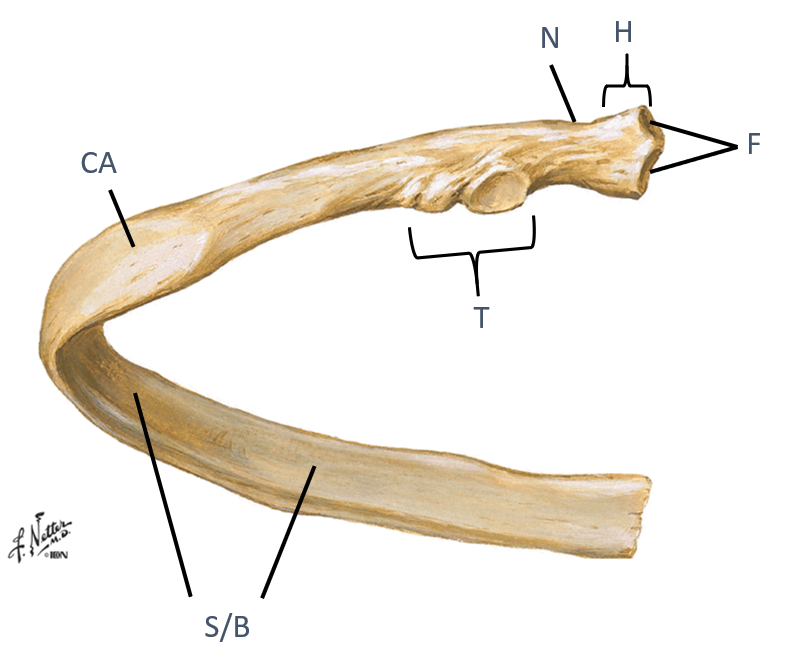

Identify the landmarks of a typical rib?

Head (H)

Neck

(N)

Tubercle (T)

Shaft/body (S/B)

Costal angle (CA)

look at picture

the head of a typical rib has what that do what?

what does the tubercle articulate with?

how would you describe the shaft/body region?

what is the costal angle a common site for?why is that?

Have facets (F) that articulate with two different vertebrae

Tubercle (T)...articulates with transverse process

Shaft/body (S/B)...thin, flat portion

Costal angle (CA)...common site of rib fracture, weakest point of the rib